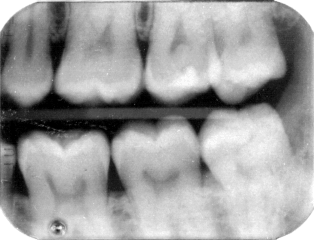

Molars

March 98

My left side.